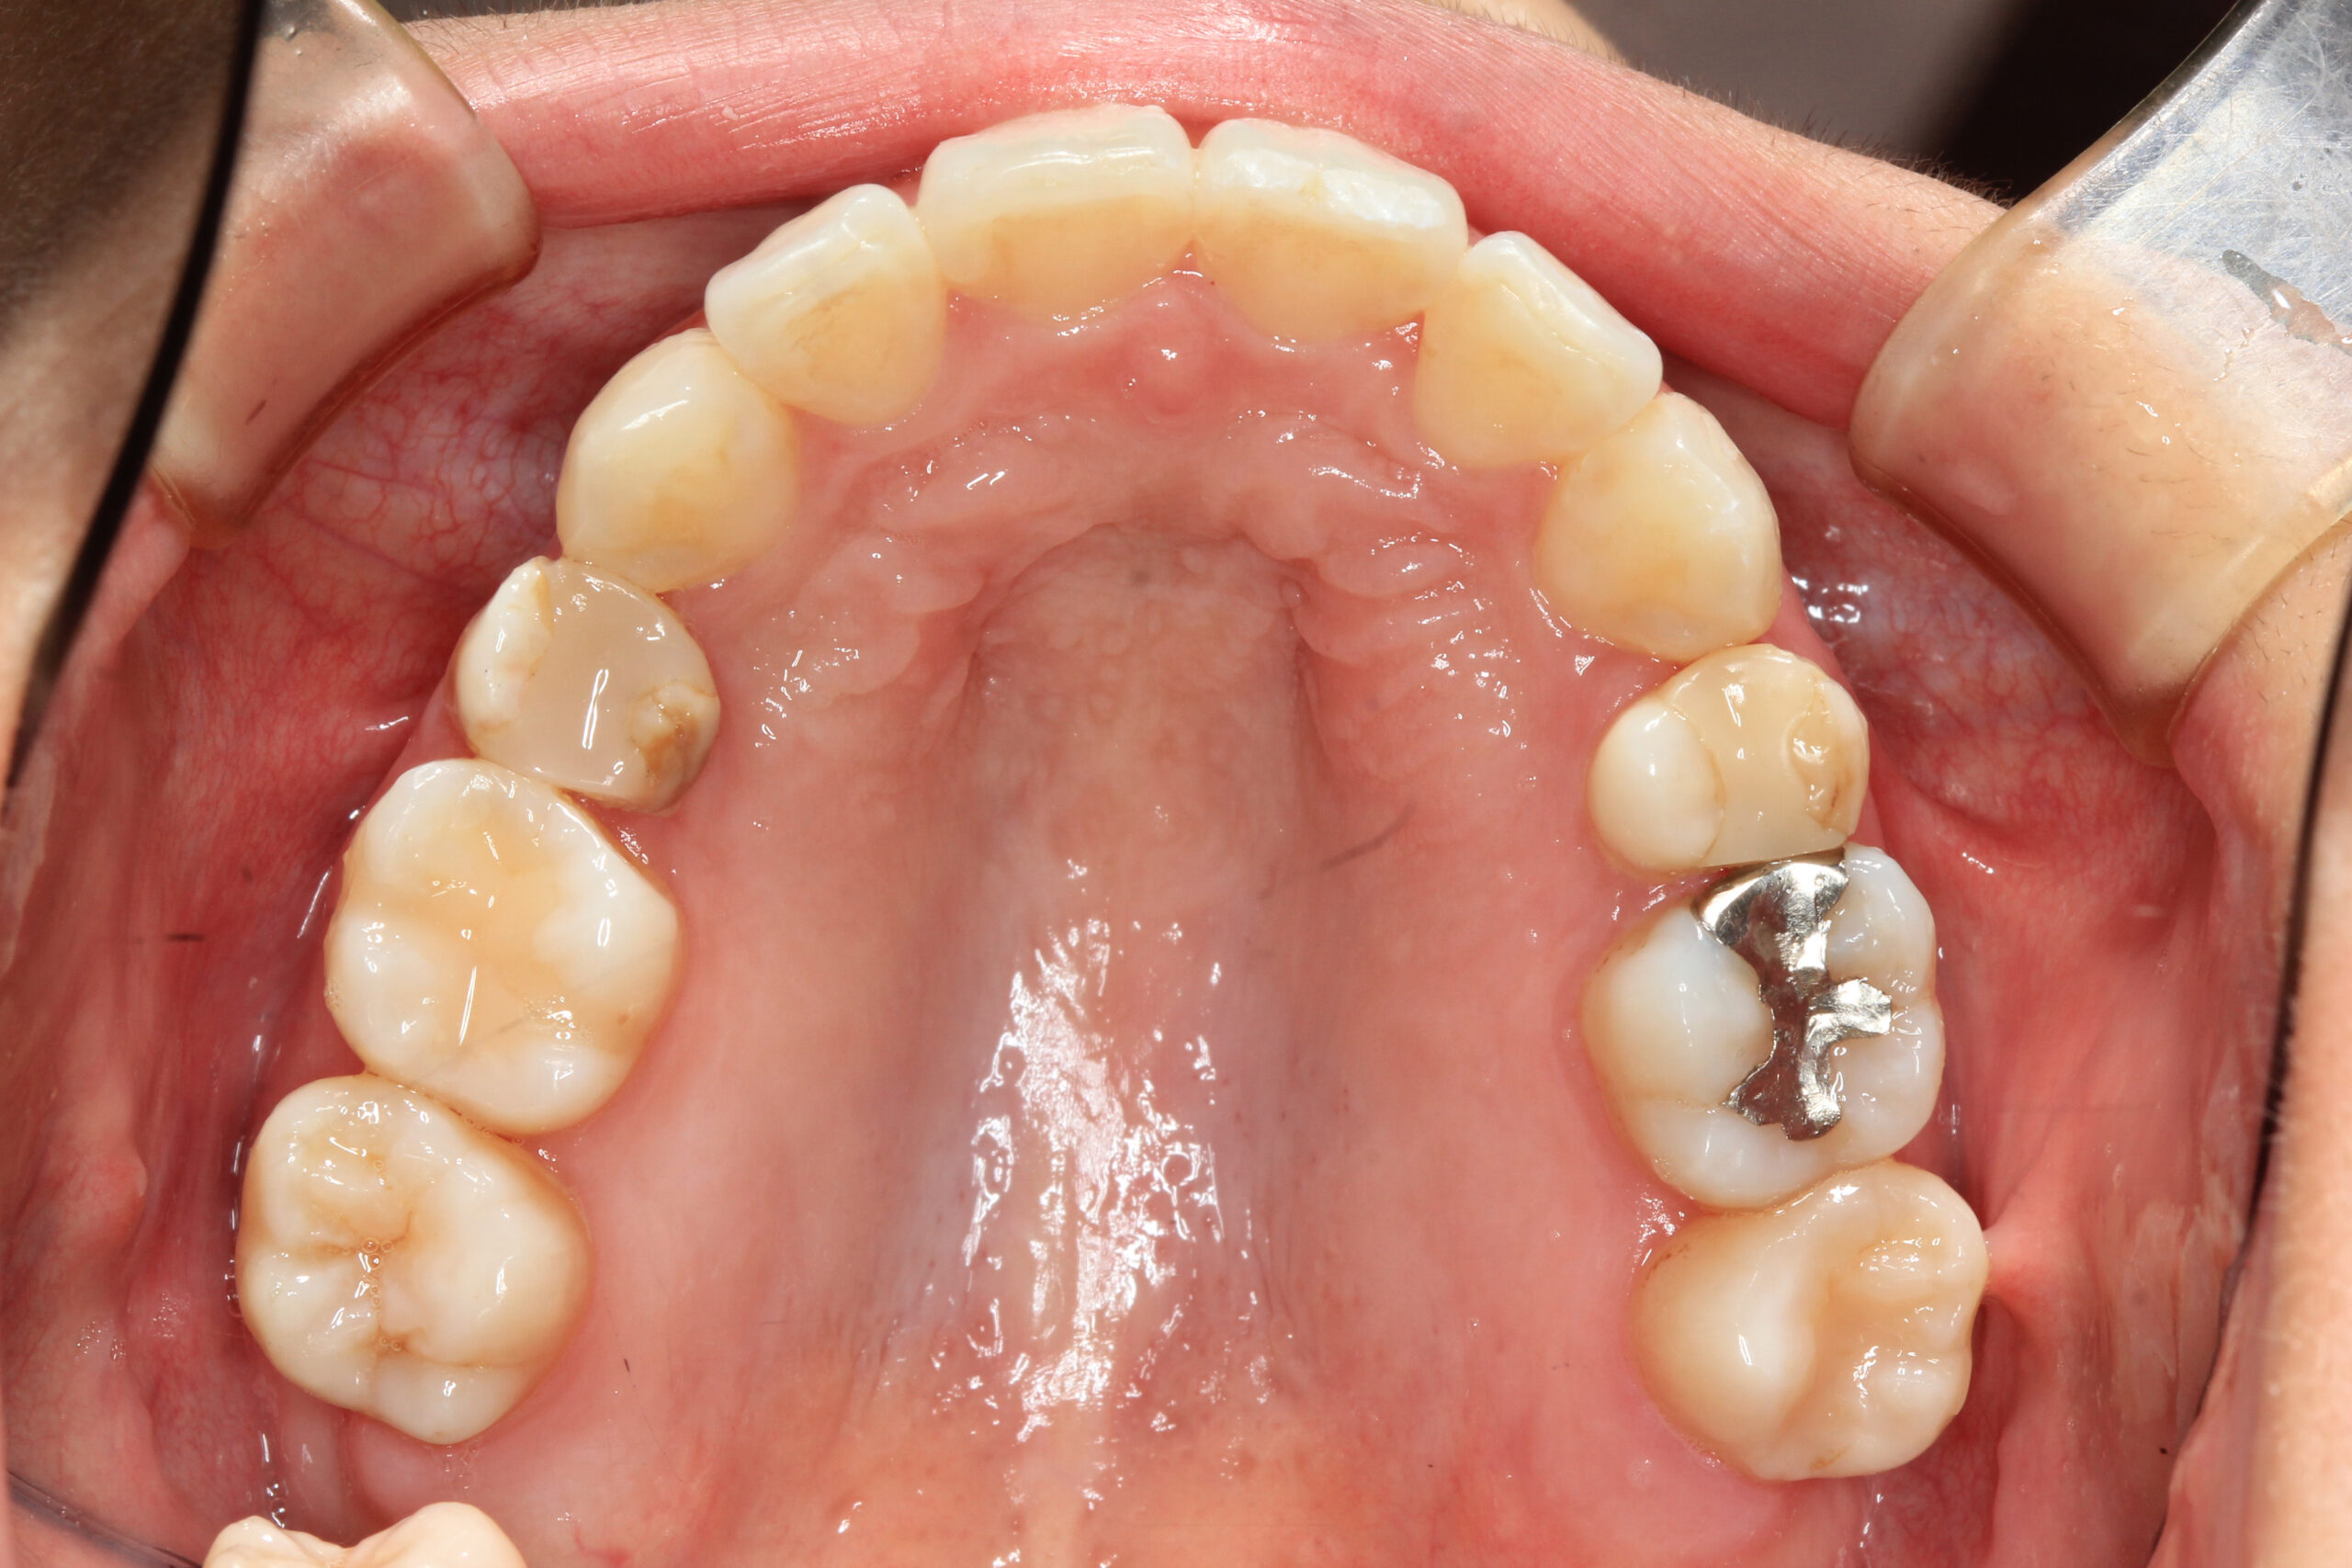

こちらのケースはアーチ形状の乱れと上下の奥歯の咬む位置のズレにより前歯が前突し、犬歯が飛び出し

ガタガタの歯並びとなっていました、

上顎のみ左右の小臼歯を抜歯する事により前突を改善し、アーチを拡大する事により叢生も改善しました。

又抜歯する事により起こる嚙み合わせの深さは当院自慢の自家製バイトアップジグにより改善しました。

かなり綺麗に改善出来た症例です。